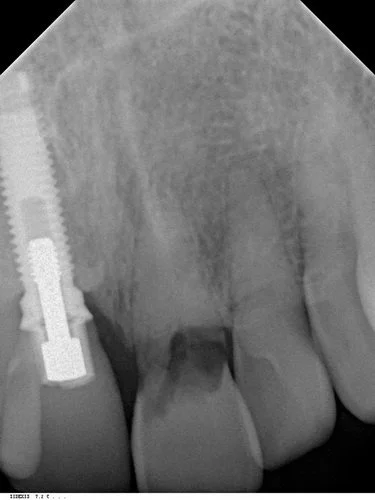

Tooth 21 was removed and due to excellent primary stability being achievable, with good interproximal bone height (Tarnow 1998) a Replace Select implant was placed immediately, with 40+ Ncm of torque being achieved. This allowed for placement of an immediate provisional restoration. The patient’s natural crown was used along with a titanium provisional abutment to construct a pleasing provisional restoration.

The photo below shows the post operative result one hour after extraction. Note the relative continued eruption (and alveolar bone growth) of the surrounding dentition compared to implant crown 11 placed 20 years ago. This is a common problem when implants are placed in young patients in the aesthetic zone.